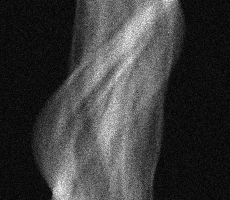

Multi-modality (or multi-channel) imaging is becoming increasingly important and more widely available, e.g. hyperspectral imaging in remote sensing, spectral CT in material sciences as well as multi-contrast MRI and PET-MR in medicine. Research in the last decades resulted in a plethora of mathematical methods to combine data from several modalities. State-of-the-art methods, often formulated as variational regularization, have shown to significantly improve image reconstruction both quantitatively and qualitatively. Almost all of these models rely on the assumption that the modalities are perfectly registered, which is not the case in most real world applications. We propose a variational framework which jointly performs reconstruction and registration, thereby overcoming this hurdle. Numerical results on simulated and real data show the potential of the proposed strategy for various applications in multi-contrast MRI, PET-MR, and hyperspectral imaging: typical misalignments between modalities such as rotations, translations, zooms can be effectively corrected during the reconstruction process. Therefore the proposed framework allows the robust exploitation of shared information across multiple modalities under real conditions.

翻译:多模式(或多通道)成像越来越重要,而且越来越普及,例如遥感中的超光谱成像、材料科学中的光谱CT以及医学中的多调MRI和PET-MR等,过去几十年的研究产生了大量数学方法,将多种模式的数据结合起来。通常作为变异性正规化的先进方法表明,在数量和质量上都大大改进了图像重建。几乎所有这些模型都基于这样一种假设,即模式已经完全登记,而在大多数现实世界应用中情况并非如此。我们提议了一个变通框架,共同进行重建和登记,从而克服这一障碍。模拟和实际数据的数字结果显示,拟议的多调MRI、PET-MR和超光谱成像的各种应用战略具有潜力:在重建过程中可以有效地纠正诸如轮换、翻译、缩影等模式之间的典型的不匹配。因此,拟议的框架允许在现实条件下,在多种模式中大力利用共享的信息。